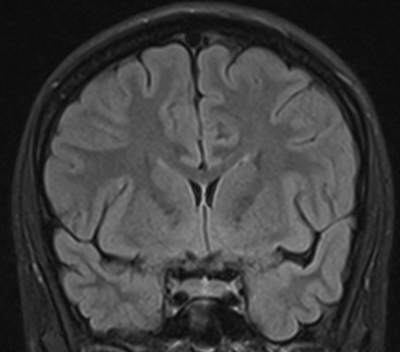

Temporallappen er afgrænset opad til mod lateral fissuren (fissura Sylvii), posteriort mod occipitallappen, postero superiort mod parietallappen, inferiort mod gulvet af fossa crani media, og medialt mod de præpontine cisterne og mod hjernestammen posteriort. Den mesiale del af temporallappen er beskrevet mere i detaljer i siden om Hippocampus. Husk at gyri og sulci er "koncepter", de er ikke altid kontinuerlige, en gyrus kan således krydses af en sulci og stadig være den samme på den anden side af den pågældende sulci, eller splittes i to parallelle som tilsammen udgør en navngiven sulci. I figurene til høje er angivet såvel de normale gyrus navne, som de mere enkle T1-T5, T6 udgøres af hippocampus. Lateralsiden af temporallappen udgøres af tre gyri adskilt af to sulci. Gyrus superior (T1) og gyrus medius (T2) adskilles af sulcus superior, mens gyrus medius og gyrus inferior adskilles af sulcus inferior. Den inferior flade af temporallappen, som hviler på gulvet af fossa crani media, udgøres af 3 gyri adskilt af to sulci. Den mest lateral gyrus er gyrus inferior (T3) som er afskilt fra gyrus fusiforme (T4) af en inkomplet sulcus occipito-temporale, mens gyrus fusiforme (T4) er adskilt fra gyrus parahippocampale (T5) af sulcus colatteralis. Dybden af sulcus colatteralis prominere ind i temporalhornet af lateralventriklen som prominentia colatteralis. Den superiore flade af temporallappen grænser op mod Insula inferiore halvdel. Den forreste del af denne flade er konkav og matcher den anteriore inferiore konvekse form af Insula, mens den posteriore supriore flade en med plan. Denne forskel kan tydligt erkendes på coronale MR-skanningssnit. Overgangen mellem den konkave og den plane den af temporallappens superiore flade markere lokalisationen af Heschel's gyrus. Heschel's gyrus har et skråt forløb fra antero-lateralt til postero-medialt. Lateralt findes Heschel's gyrus lige overfor gyrus postcentral i parietallappen adskilt af lateralfissuren. Følges Heschel's gyrus medialt posteriort peger den mod antrum af ventrikelsystem lige posteriort for thalamus. Den mesiale flade af temporallappen er en konkav flade som omgrænser hjernestammen.